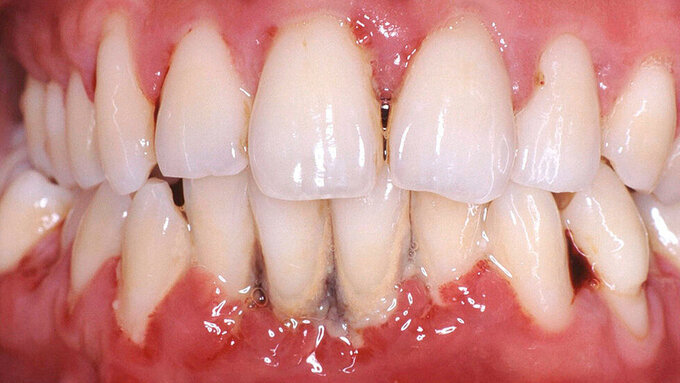

Eine erhöhte Zahnmobilität bei Patienten mit Parodontitis kann infolge einer parodontalen Entzündung auftreten, die Folge einer okklusalen Dysfunktion sein oder bei einem reduzierten Parodont vorkommen, wenn sich das Rotationszentrum der Zähne aufgrund des Knochenabbaus nach apikal verschoben hat und somit der Hebel, auf den die Kaukräfte einwirken, größer geworden ist (Abbildung 1) [Mühlemann, 1960]. Dies kann den oralen Komfort der Patienten – inklusive Phonetik, Abbeiß- und Kaufunktion – stark beeinträchtigen und sich auch auf die Ästhetik auswirken. Während die Mobilität der Zähne bei parodontalen Entzündungen nach einer systematischen Parodontitistherapie abnehmen kann und daraus resultierende okklusale Frühkontakte durch gezieltes Einschleifen, gegebenenfalls in Kombination mit Schienungen, adressiert werden können, existiert keine kausale Therapie zur Reduktion der Mobilität von Zähnen mit reduziertem Parodont bei horizontalem Knochenverlust.

Unterkieferfrontzähne sind mit Abstand die am häufigsten von einer Zahnlockerung betroffenen Zähne, gefolgt von Oberkieferfrontzähnen [Gupta et al., 2023]. Zahnlockerungen von Inzisivi korrelieren mit dem Attachmentlevel und werden vorwiegend bei Patienten mit Parodontitis im Stadium IV festgestellt [Khoo und Watts, 1988; Deng et al., 2022].

Eine erhöhte Mobilität von parodontal betroffenen Zähnen kann auch nach der Durchführung einer systematischen Parodontitistherapie bestehen bleiben, wenn infolge der parodontalen Destruktion nur ein stark reduziertes Parodont verbleibt. Im reduzierten Parodont führen die gleichen Kräfte aufgrund geänderter Hebelverhältnisse zu einer stärkeren Auslenkung der Zähne (Abbildung 1). Die Schienung gelockerter Frontzähne mit reduziertem Parodont verbessert die Phonetik und die Fähigkeit, abbeißen zu können. Schienungen können eine langzeitprovisorische Lösung für mobile Zähne mit reduziertem Parodont sein.